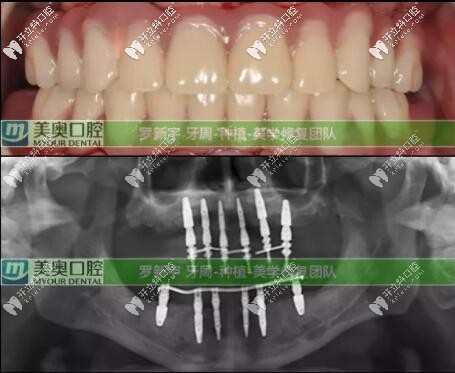

接著就是種植牙修復(fù)計(jì)劃:根據(jù)臨床上的口腔數(shù)據(jù),根據(jù)顧客的實(shí)際情況選擇了Straumann? Pro Arch無牙頜種植修復(fù)解決方案,拔除全部松動(dòng)的余留牙,雖然犧牲可能有點(diǎn)大,但換來的是全口好牙還有自信。

全口即刻負(fù)重種植就是:在當(dāng)天種植并完成臨時(shí)修復(fù),PS:臨時(shí)修復(fù)是指臨時(shí)牙冠。為患者帶上臨時(shí)牙,可實(shí)現(xiàn)當(dāng)天吃蘋果的愿望。即刻修復(fù)就是這么快。后期又進(jìn)行了為期六個(gè)月的復(fù)診和跟蹤治療;

六個(gè)月后口腔檢查評價(jià):種植體全部存留、臨時(shí)修復(fù)體存留、終末修復(fù)體(長久性的牙冠)存留;可以說這次種植修復(fù)是很成功的。